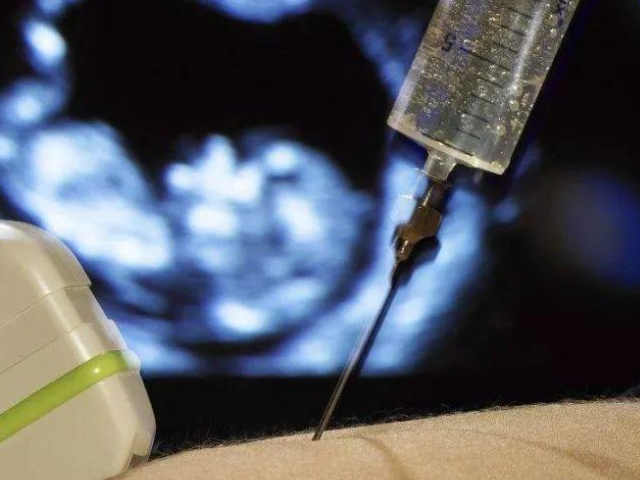

做绒毛穿刺检查的时候用一根很细的针穿刺到胎盘的组织中去,取20~40毫克的绒毛量出来进行检查。绒毛穿刺检查方法总共有4种,可以经阴道,也可以经腹进行。

腹部皮肤局麻,穿刺针经腹壁进入胎盘绒毛部分,用空针管吸取少量绒毛送检。

在超声扫描引导下,医生将导管(一种易弯曲的细管)经阴道、子宫颈送入胎盘绒毛部分,用空针管吸取少量绒毛送检。有子宫颈病变,生殖道感染,如生殖道疱疹、淋病、慢性宫颈炎等,不宜经阴道取样。